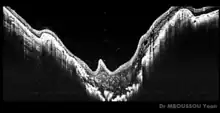

On fundoscopic examination, there are three principal findings comprising the anomaly:[5]

- an enlarged, funnel-shaped excavation in optic disc

- an annulus or ring of chorioretinal pigmentary changes surrounding the optic disc excavation

- a central glial tuft overlying the optic disc